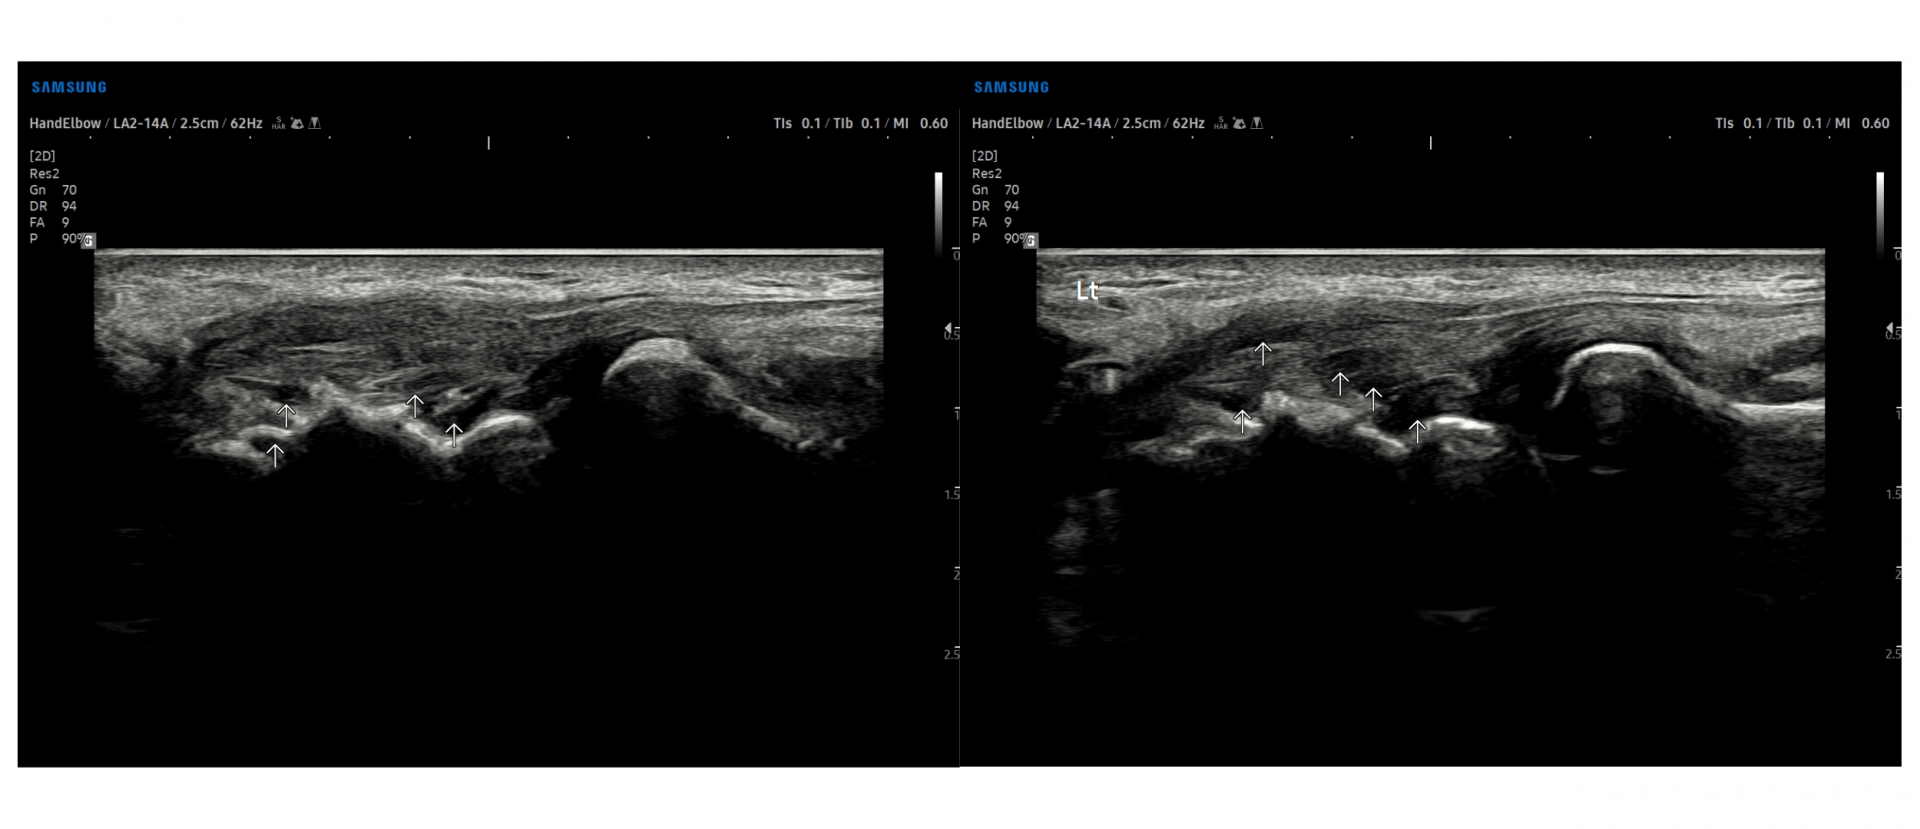

- 치료기간 : 25 . 6 . 9 ~ 25 . 10 .27

- 치료횟수 : 4 사이클(20) 회

치료전

치료 후

힘줄 두께 감소 및 전체적인 파열 부위 축소 & 골극 감소

-> 검사상 파열은 여전히 있지만 운동 이후에도 통증이 크게 없어서 치료 종료 후 3~4주정도 텀 두고 관찰 예정